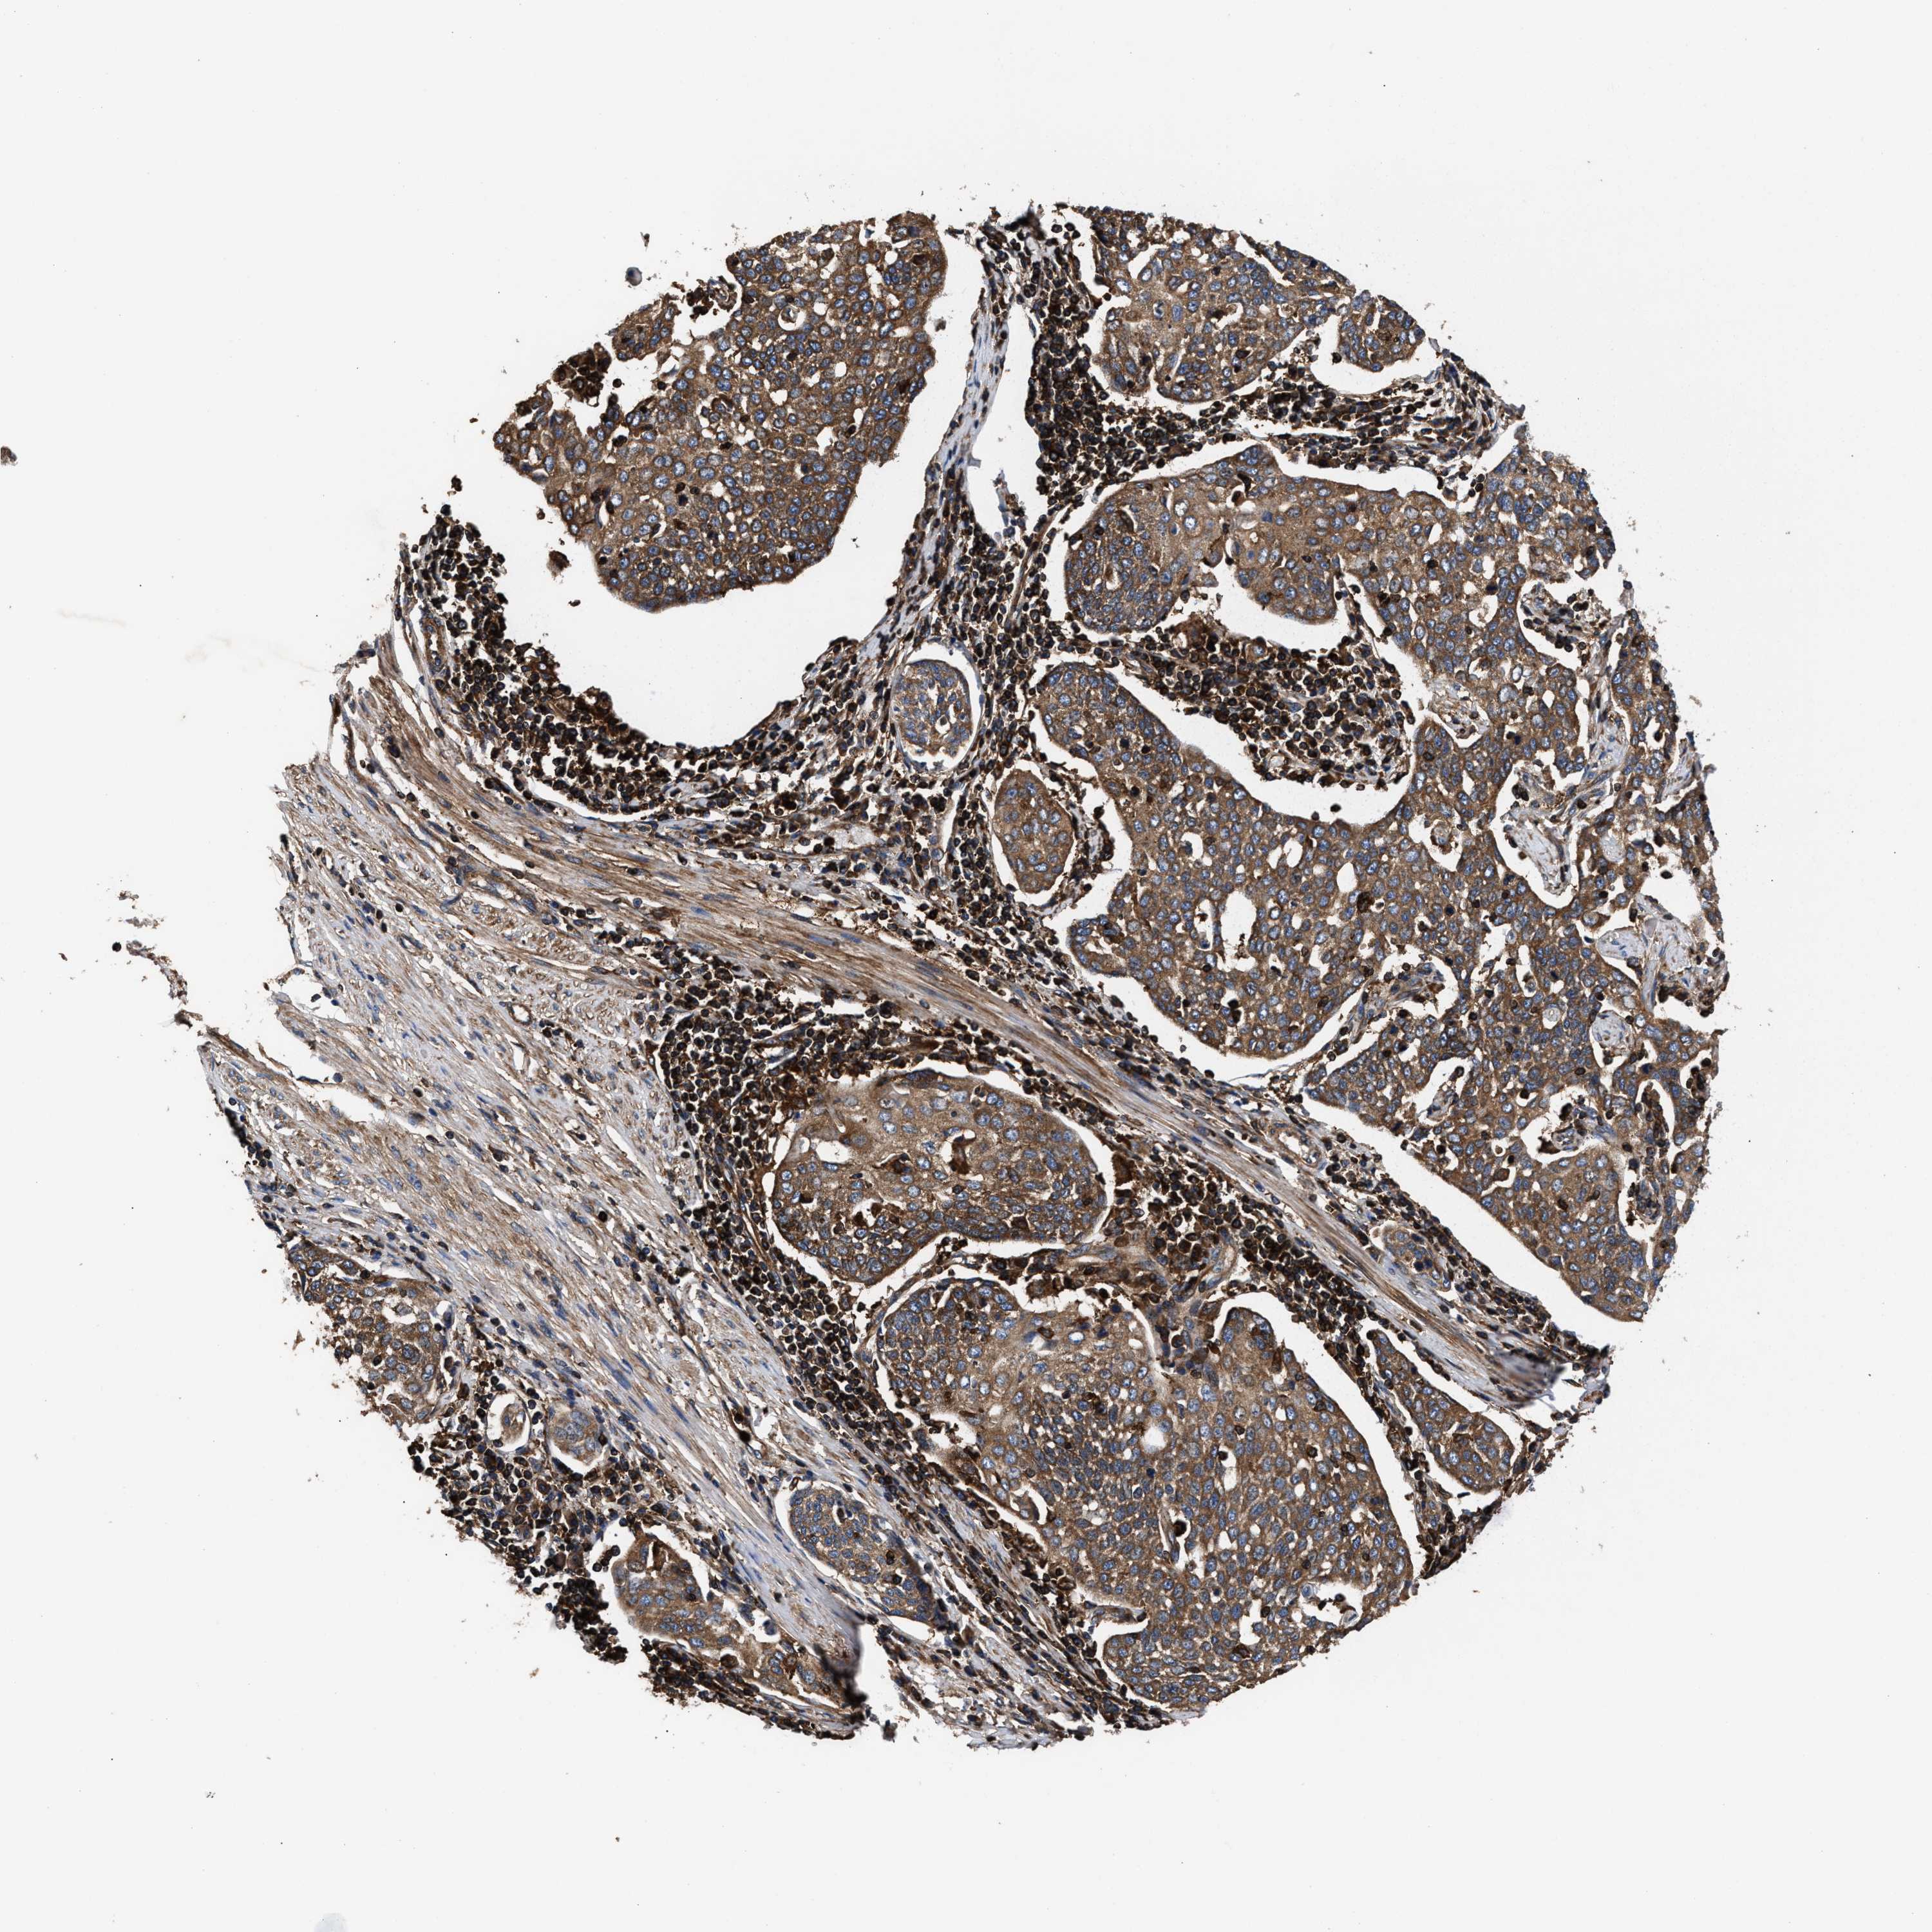

CERVICAL CANCER - Protein expressioni

A mouse-over function shows sample information and annotation data. Click on an image to view it in a full screen mode. Samples can be filtered based on level of antibody staining by selecting one or several of the following categories: high, medium, low and not detected. The assay and annotation is described here.

Note that samples used for immunohistochemistry by the Human Protein Atlas do not correspond to samples in the TCGA dataset.

Antibody stainingi

Antibody staining in the annotated cell types in the current human tissue is reported as not detected, low, medium, or high, based on conventional immunohistochemistry profiling in selected tissues. This score is based on the combination of the staining intensity and fraction of stained cells.

Each image is clickable and will lead to virtual microscopy that enables deeper exploration of all samples and also displays staining intensity scores, fraction scores and subcellular localization as well as patient and tissue information for each sample.

Antibody HPA021176

Antibody HPA021177

Antibody HPA027736

Squamous cell carcinoma, NOS

Adenocarcinoma, NOS